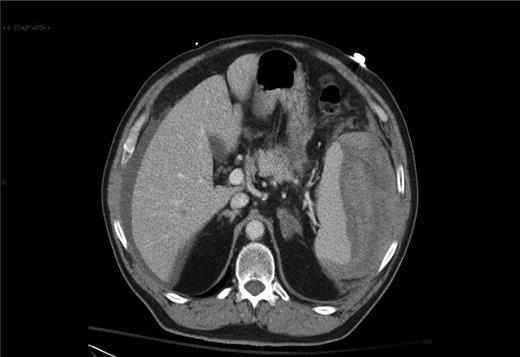

In the emergency department on current presentation, the patient was hypotensive with a blood pressure of 76/40. Physical examination revealed a soft, distended abdomen that was tender in the left upper quadrant. The patient demonstrated no rebound tenderness or guarding. CT scan of the chest, abdomen and pelvis revealed hemoperitoneum and a possible splenic laceration (Fig. 2). Laboratory work showed hemoglobin of 10.9 g/dl and a hematocrit of 30.4%. The patient was optimized for emergent exploratory laparotomy.